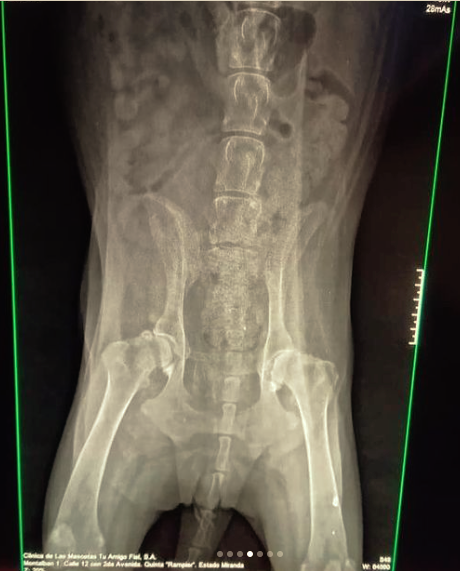

Bianca es una perra samoyedo que parece un copo de algodón flotando cuando la ven pasar junto a su manada. Ella es buena, noble, inteligente y por esa actitud de perra sabia y dulce que le han dado los años se ha ganado el amor y respeto de los vecinos de Montalbán, donde suele pasear todas las tardes o noches junto a sus hermanos perros donde ejerce una especie de matriarcado de perra Alfa. Anoche Bianca fue atropellada por una persona que en su afán para entrar al estacionamiento de uno de los edificios de Juan Pablo II, la arolló, ante los ojos de amigos que vieron impotentes como la camioneta le pasaba por encima, Bianca que ya venía sufriendo de displasia de caderas, se encuentra ahora en su casa sufriendo y sin poder caminar, ya se le puso una inyección para calmar sus dolores, pero para saber que problemas atraviesa debido al accidente y si tiene alguna fractura, o hemorragia interna se le debe hacer una radiografía de tres vistas, así como pagar la consulta y su posible operación.

Bianca se encuentra postrada, no puede caminar y tiene retención de orina, así como inflamación de hígado.